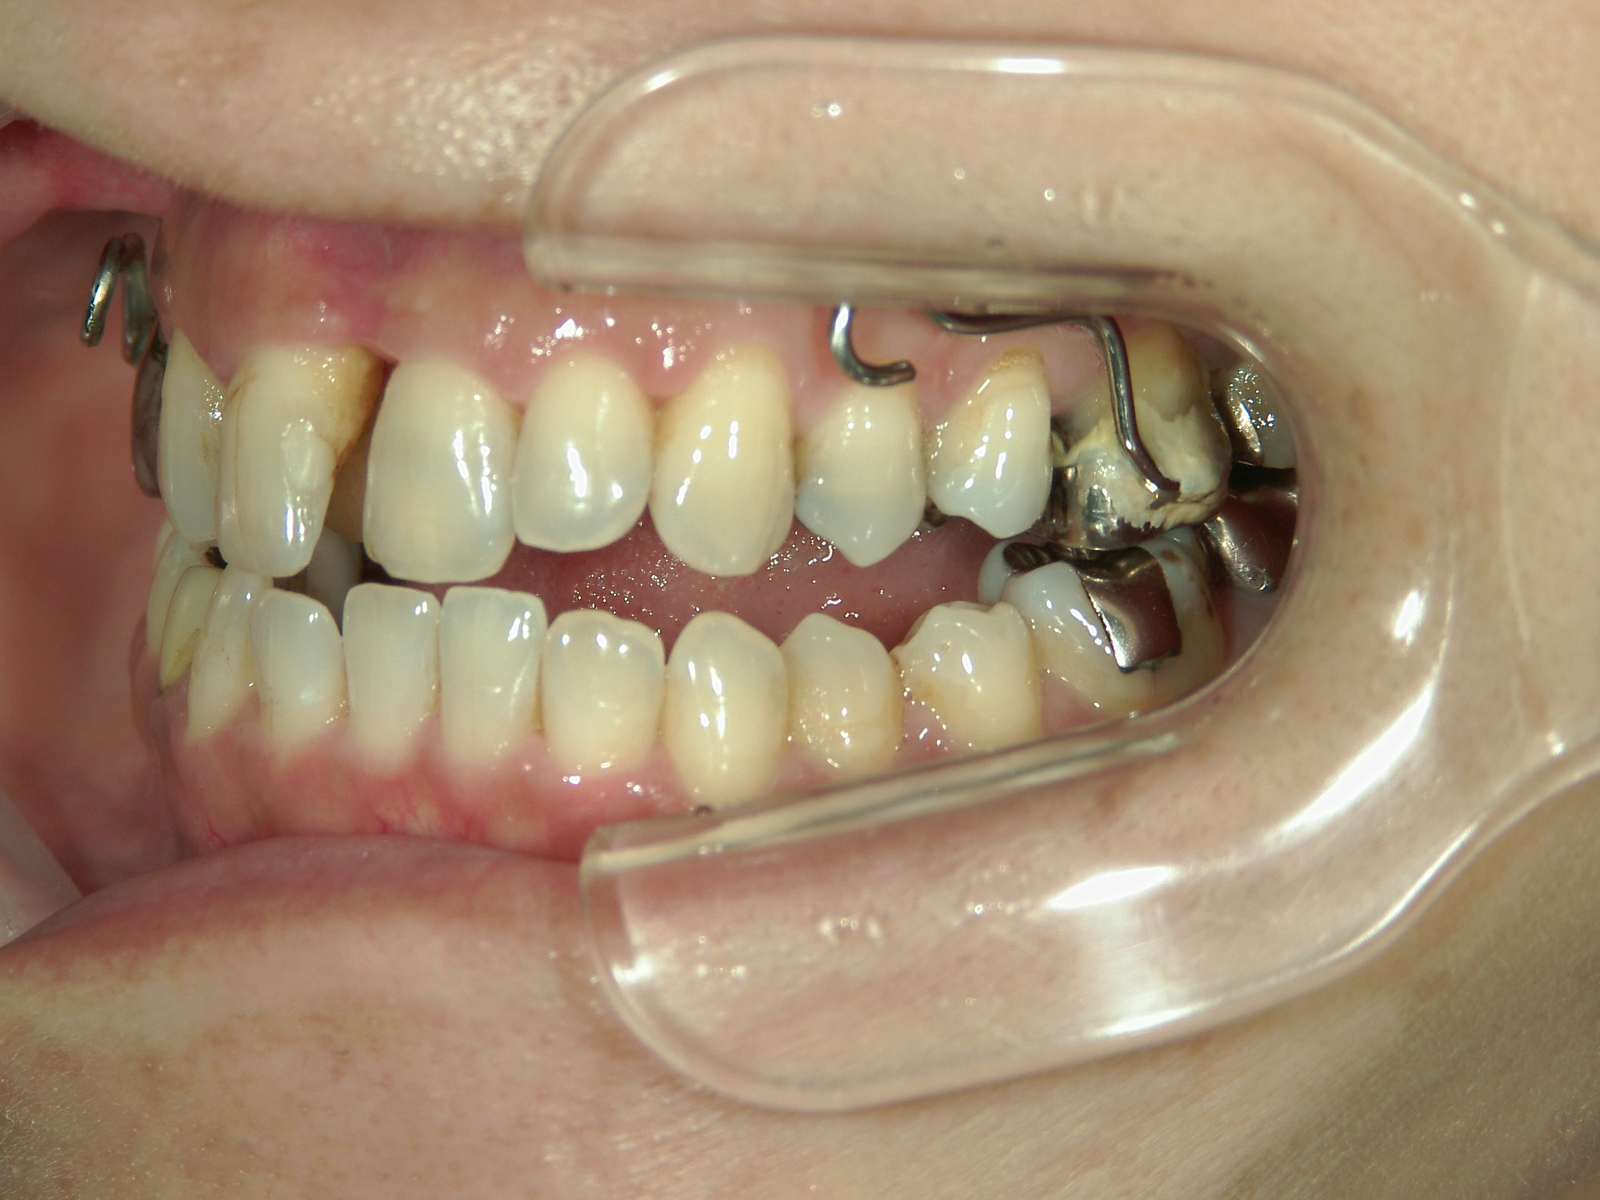

主訴: 受け口、歯並びが気になる。

①患者様はインビザライン矯正をご希望でしたが、上顎骨が小さく、受け口になっているので、インビザライン矯正で治療するために「骨切断OPE」「矯正装置(MSE+フェイスマスク)」で上顎骨を拡大しました。

②右上前歯が内側に入っているため、歯列に入る隙間を作るためにワイヤー矯正を併用し、右上前歯を出しました。

③矯正装置を除去し、インビザライン矯正で歯列を整えました。